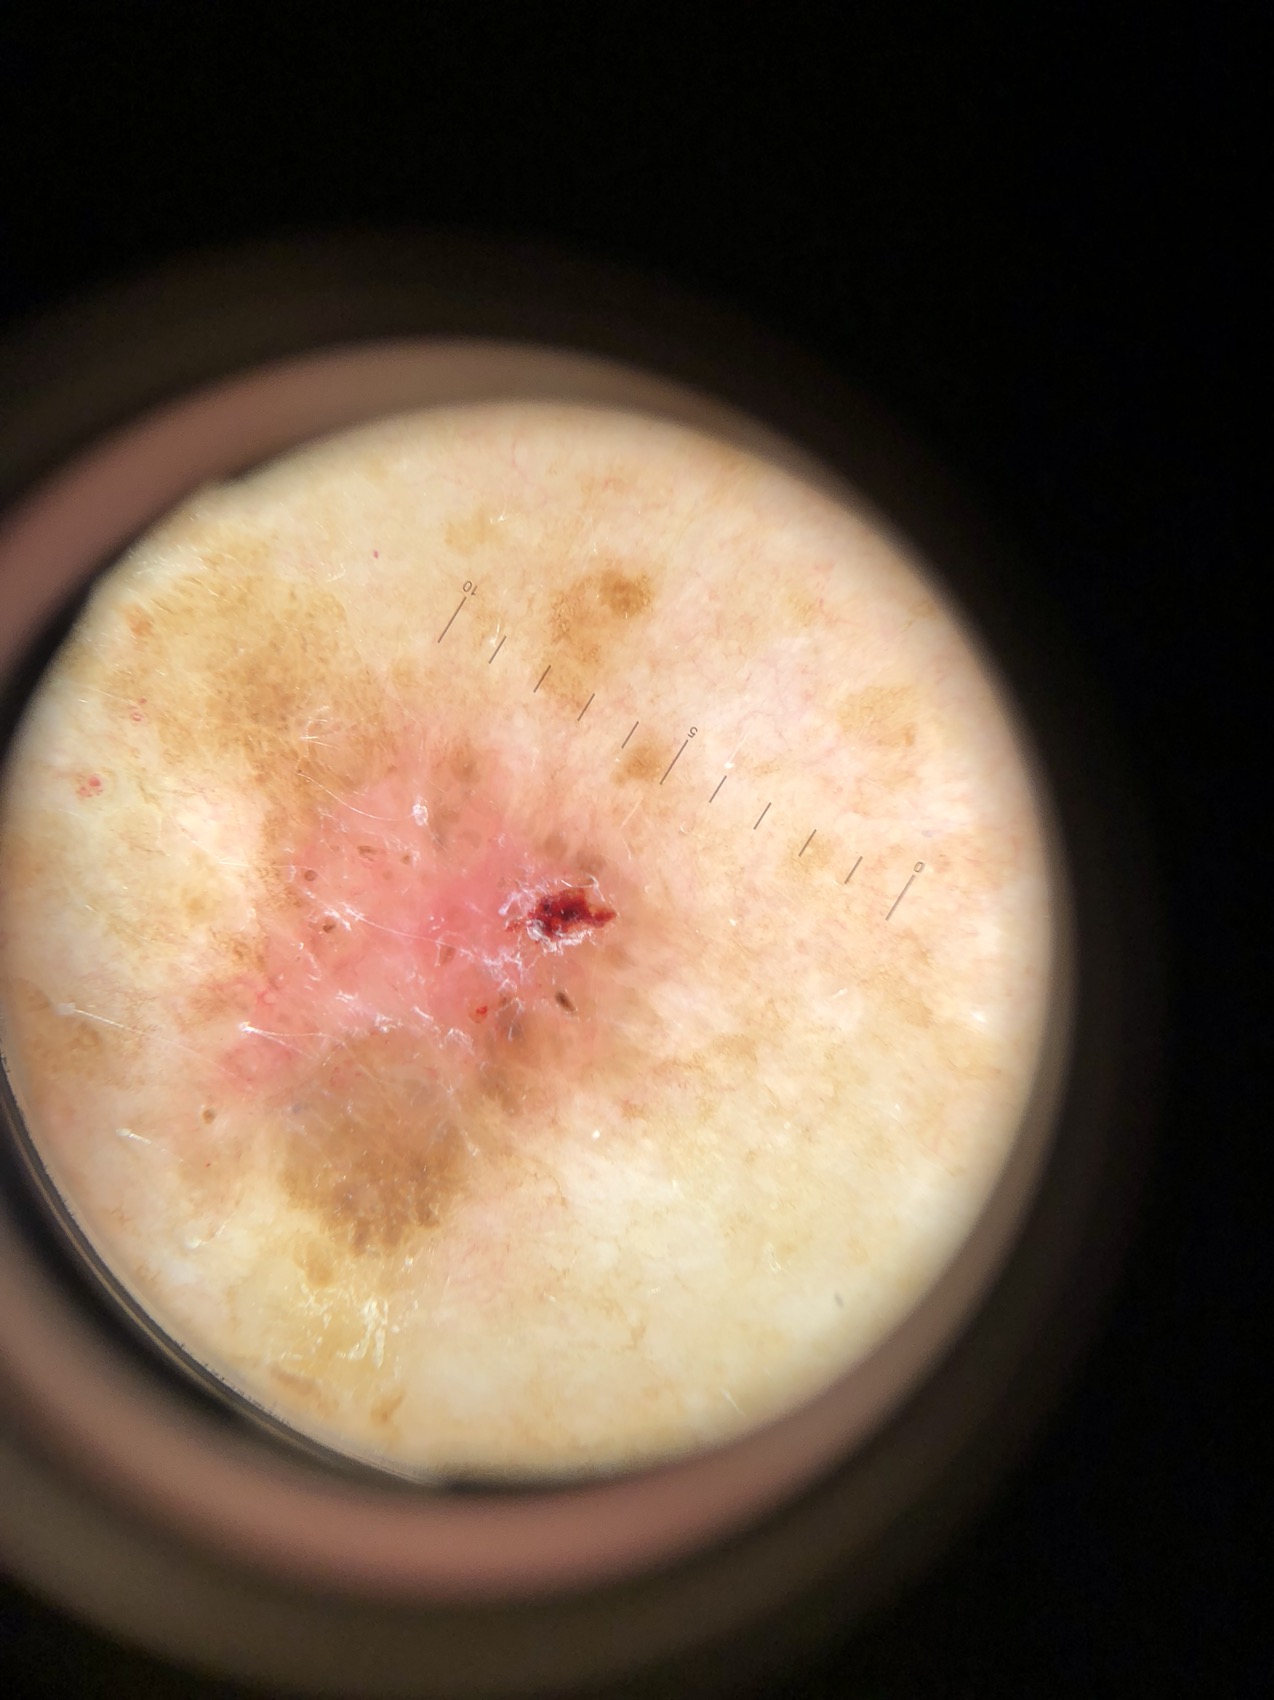

Seuraavana muutamia luomikuvia ja heti perään valokuva joka otettu dermatoskoopin kautta. Testaa itsesi jos tunnistat ko. muutokset!

Potilas 4, rintakehä:

Potilas 4: rintakehällä pinnallisesti leviävä melanooma.